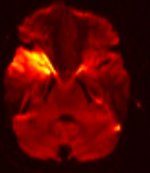

MR-Angiographie (MRA) meiner Halsgefäße |

|

Zwei Arterienpaare übernehmen die Blutzufuhr zum Gehirn (Arteria

carotis interna) und (Arteria vertebralis).

Beide vereinigen sich in der Hirnbasis zu einem

ringförmigen Arterienkreis, dem Circulus Willisii. Vom

Willisi-Kreis gehen paarweise die drei großen Hirnarterien ab,

die vordere, mittlere und hintere Hirnarterie. |

MR-Angiographie (MRA) meiner

Hirnbasisarterien

(Circulus Willisi) |

gut sichtbar distale Stenose Arteria

carotis rechts |